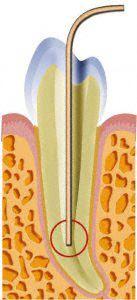

Unter örtlicher Betäubung ist die Behandlung meist schmerzfrei. Nach Entfernung der Karies und nach der Schaffung eines Zugangs in den Zahn werden die Kanaleingänge dargestellt und die Länge jedes einzelnen Kanals wird möglichst exakt unter Anwendung von Röntgen ausgemessen. Abhängig vom zu behandelten Zahn kann die Anzahl der Kanäle stark variieren.

Danach erfolgt die Aufbereitung mit Hilfe von speziellen, sehr feinen Instrumenten aus einer Nickel-Titan-Legierung oder Edelstahl und kann manuell oder maschinell erfolgen. Zusätzlich können Ultraschalinstrumente oder Laser benutzt werden.

Danach werden die Kanäle gereinigt und so ausgeformt, dass später eine dichte Wurzelfüllung möglich ist. Für eine möglichst vollständige Reinigung des Kanalsystems wird die mechanische Aufbereitung durch Spülungen mit desinfizierenden Lösungen ergänzt.